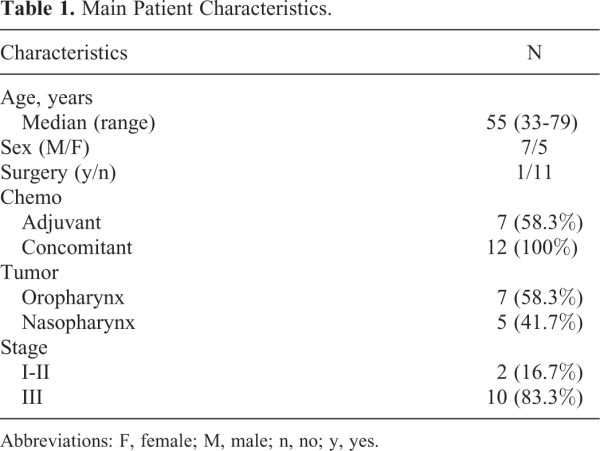

Twelve patients (median age: 55 years; range: 33-79) previously treated with IGRT at our institute were selected for this study; at the time of treatment, all patients signed an informed consent form including the use of imaging information. All patients were treated with a simultaneous integrated boost approach, delivering 54 Gy to the elective lymph nodes, 61.5/66 Gy to the tumor bed/tumor, and 69 Gy to the PET-positive volume. Seven oropharynx and 5 nasopharynx cases were considered; for 7 patients, the tumor was bilateral, whereas for 5, it was unilateral. Table 1 summarizes the main characteristics of the considered patients.

Deformable registration and contour propagation were evaluated by considering the MRI acquired before treatment (MRI_1) and a MRI scan acquired 2 to 3 months after the end of the treatment (MRI_2; days after end of RT: mean = 70, range = 42-99). Magnetic resonance imaging was performed using a 1.5-T scanner (Achieva Nova; Philips Medical Systems, Best, the Netherlands) equipped with HN combined coil. The MRI protocol included a fat-suppressed 3-dimensional (3D) T1w fast field echo sequences (Repetition Time [TR] and Echo Time [TE] shortest; field of view = 200 mm × 200 mm; matrix 224 × 221; slice thickness: 2 mm; Number of Signal Averages [NSA]: 1) acquired after the intravenous injection of gadobutrol (Gadovist; Bayer Schering, Germany) at a dose of 0.1 mmol/kg body weight. On both MRI scans, an expert radiation oncologist contoured the PGs.